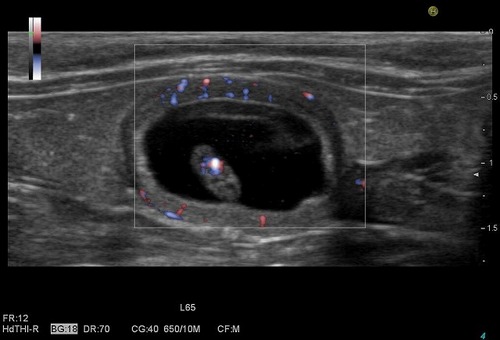

カラードプラ検査で、胎児の心臓の中の血流が赤青に色が付いて見えます。

胎児を包んでいる胎盤の中の血液の流れも赤青に色が付いて見えます。

約4mmの胎児の体の中の心臓が、力強く脈打っているのがよくわかります。

生命の力強さを感じる瞬間です。